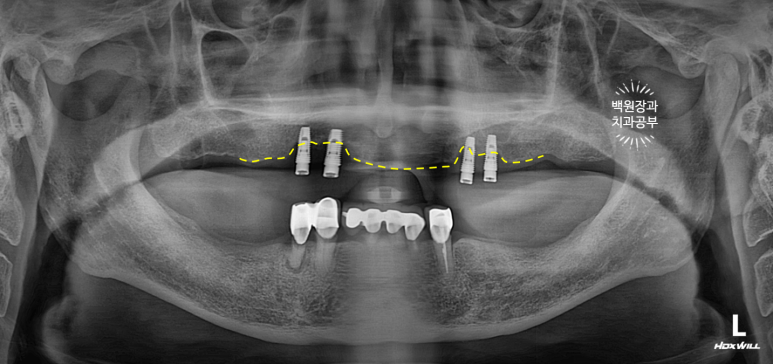

노란 점선이 보이시나요? 잇몸뼈의 높이입니다.

상당한 양의 임플란트 주변 뼈가 녹아서 없어져 버린것을 보실 수 있어요.

환자분은 임플란트를 엄청 빼고싶어 하셨습니다.

저희 치과 잘 찾아오셨습니다....!